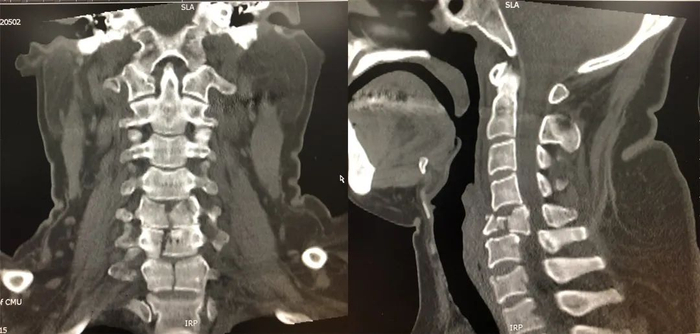

患者为外伤导致颈5椎体爆裂骨折,颈6、7椎体及椎板多处骨折。由于患者颈5椎体爆裂,颈6、7椎体骨折为纵向劈裂,手术应行颈5椎体次全切除,颈4、6、7椎体固定,但常规的颈椎前路钢板螺钉难以实现该病例的坚强固定。ACPS联合颈椎前路钢板因可实现颈椎三柱固定,非常适合于此特殊病例的治疗,但目前常规颈椎前路钢板无法与ACPS相匹配。朱悦教授团队针对该病例特点精心设计了手术方案,术前根据其颈椎3D-CT设计了具有可以匹配ACPS的钉孔、融合体与颈椎前路钢板一体化的金属3D打印假体,拟应用骨科机器人辅助ACPS技术完成本例手术。

患者术前骨折影像